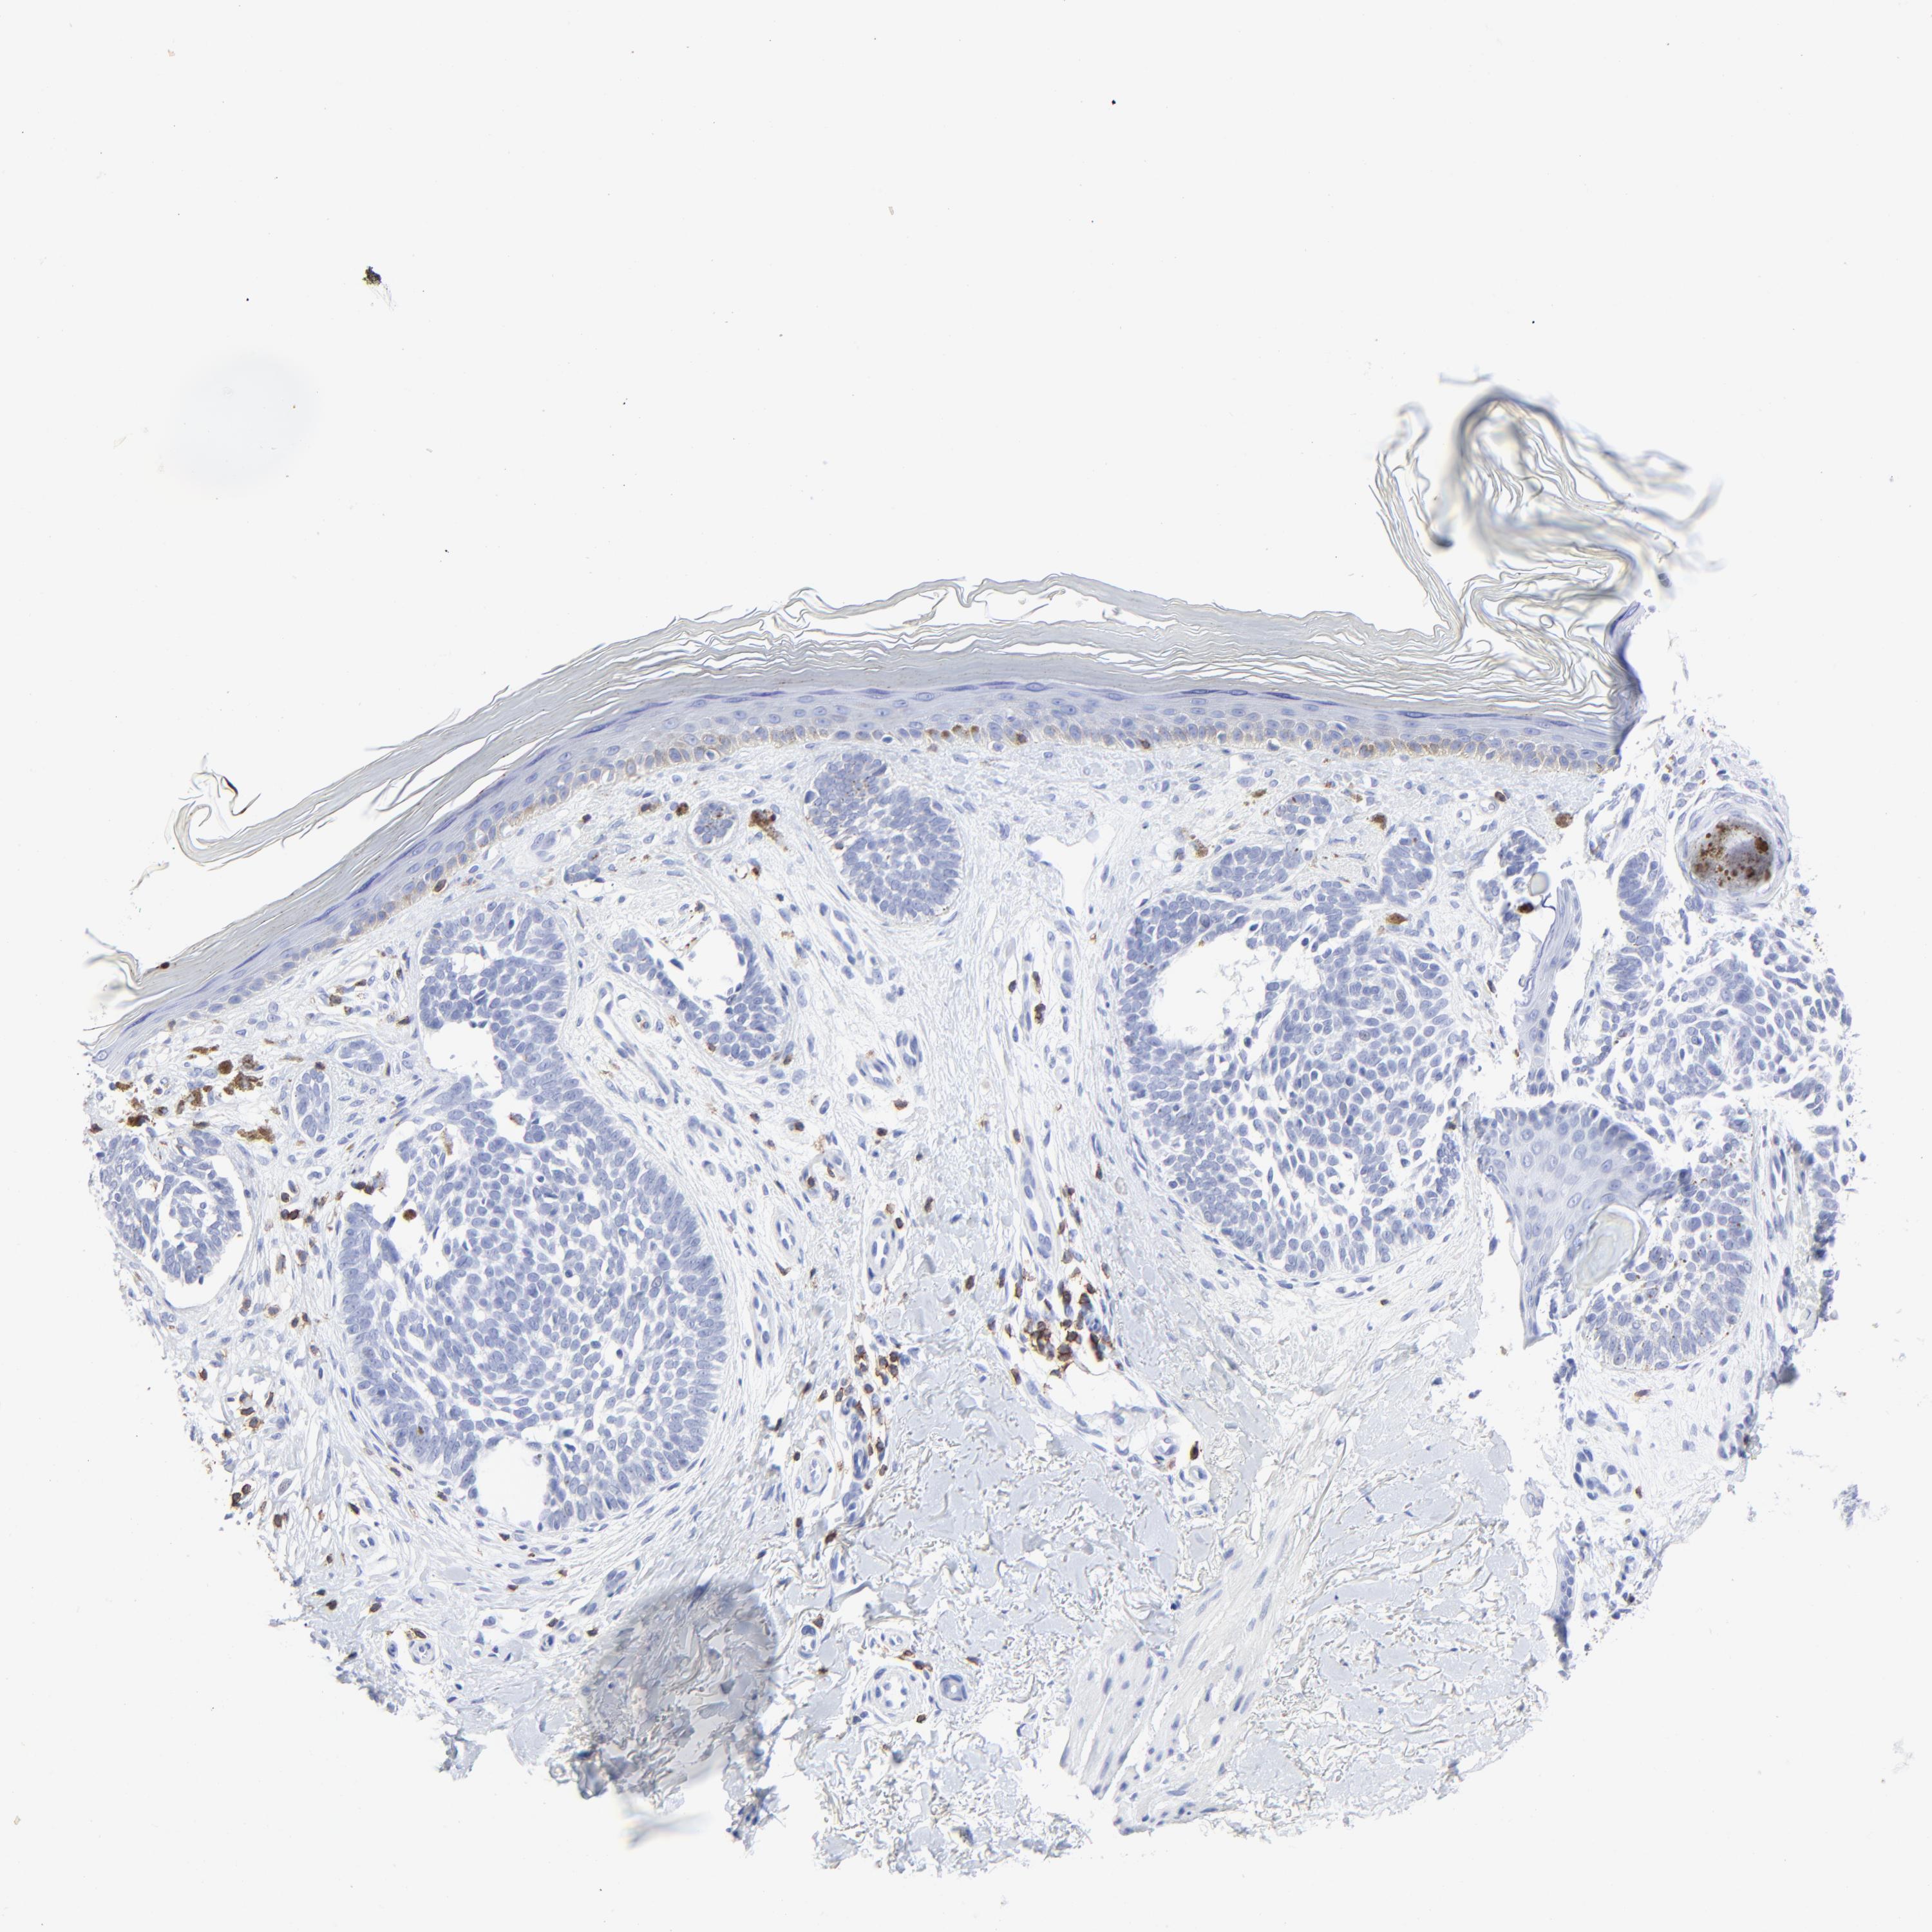

SKIN CANCER - Protein expressioni

A mouse-over function shows sample information and annotation data. Click on an image to view it in a full screen mode. Samples can be filtered based on level of antibody staining by selecting one or several of the following categories: high, medium, low and not detected. The assay and annotation is described here.

Antibody stainingi

Antibody staining in the annotated cell types in the current human tissue is reported as not detected, low, medium, or high, based on conventional immunohistochemistry profiling in selected tissues. This score is based on the combination of the staining intensity and fraction of stained cells.

Each image is clickable and will lead to virtual microscopy that enables deeper exploration of all samples and also displays staining intensity scores, fraction scores and subcellular localization as well as patient and tissue information for each sample.

Antibody HPA003494

Antibody CAB003816

Squamous cell carcinoma, NOS

Basal cell carcinoma